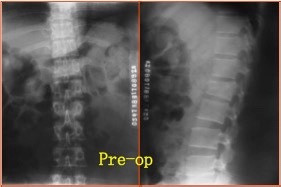

主诉:高处坠落致腰痛、活动不能1天。 现病史:患者诉于1天前不慎自3米高阳台坠落,当即感腰痛,活动不能,伴双下肢麻木。无伴昏迷、头晕等不适。遂到我院就诊,行x光检查示腰2椎体爆裂骨折,收入院。

查体:卧床状态,腰部活动不能,行走不能,腰2棘突上叩痛,压痛(+)。双下肢大腿中段以下皮肤感觉减退、肌力正常,膝反射及膝踝反射正常,双侧Babinski征(-)。 辅助检查:CT检查示腰2椎体爆裂性骨折。椎管内占位改变。

诊断:腰2椎体爆裂性骨折(AO分型:A3.1) 治疗:给予急诊行腰1-腰2椎弓根钉固定+骨折复位术。术中行椎板切除减压,用骨冲将突入椎管的骨块复位。